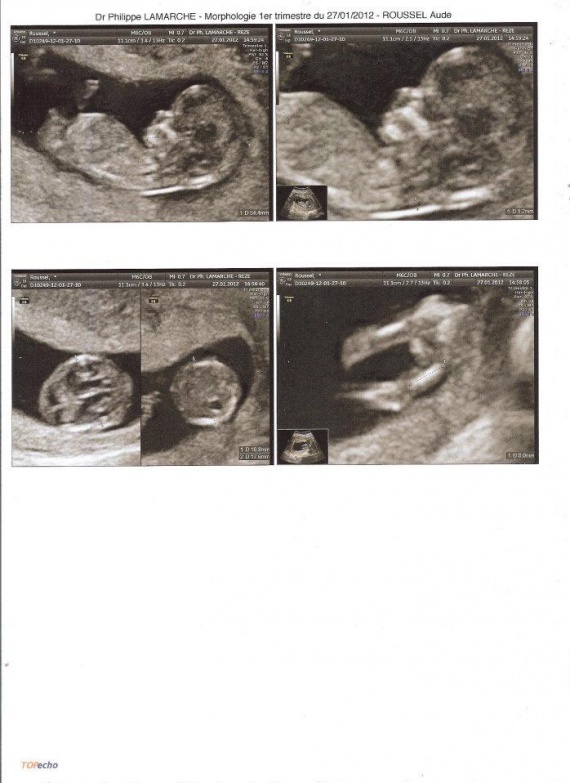

12 Semaine D Aménorrhée En Mois Echographie 12 semaine d'aménorrhée ! - Maman d'une princesse ♥

12 Semaine D Aménorrhée En Mois L'échographie des 12 Semaines - un deuxième bébé prévu pour le 28

12 Semaine D Aménorrhée En Mois Semaine 12 (SA) : Echographie officielle du 1er trimestre - Mère...Credi